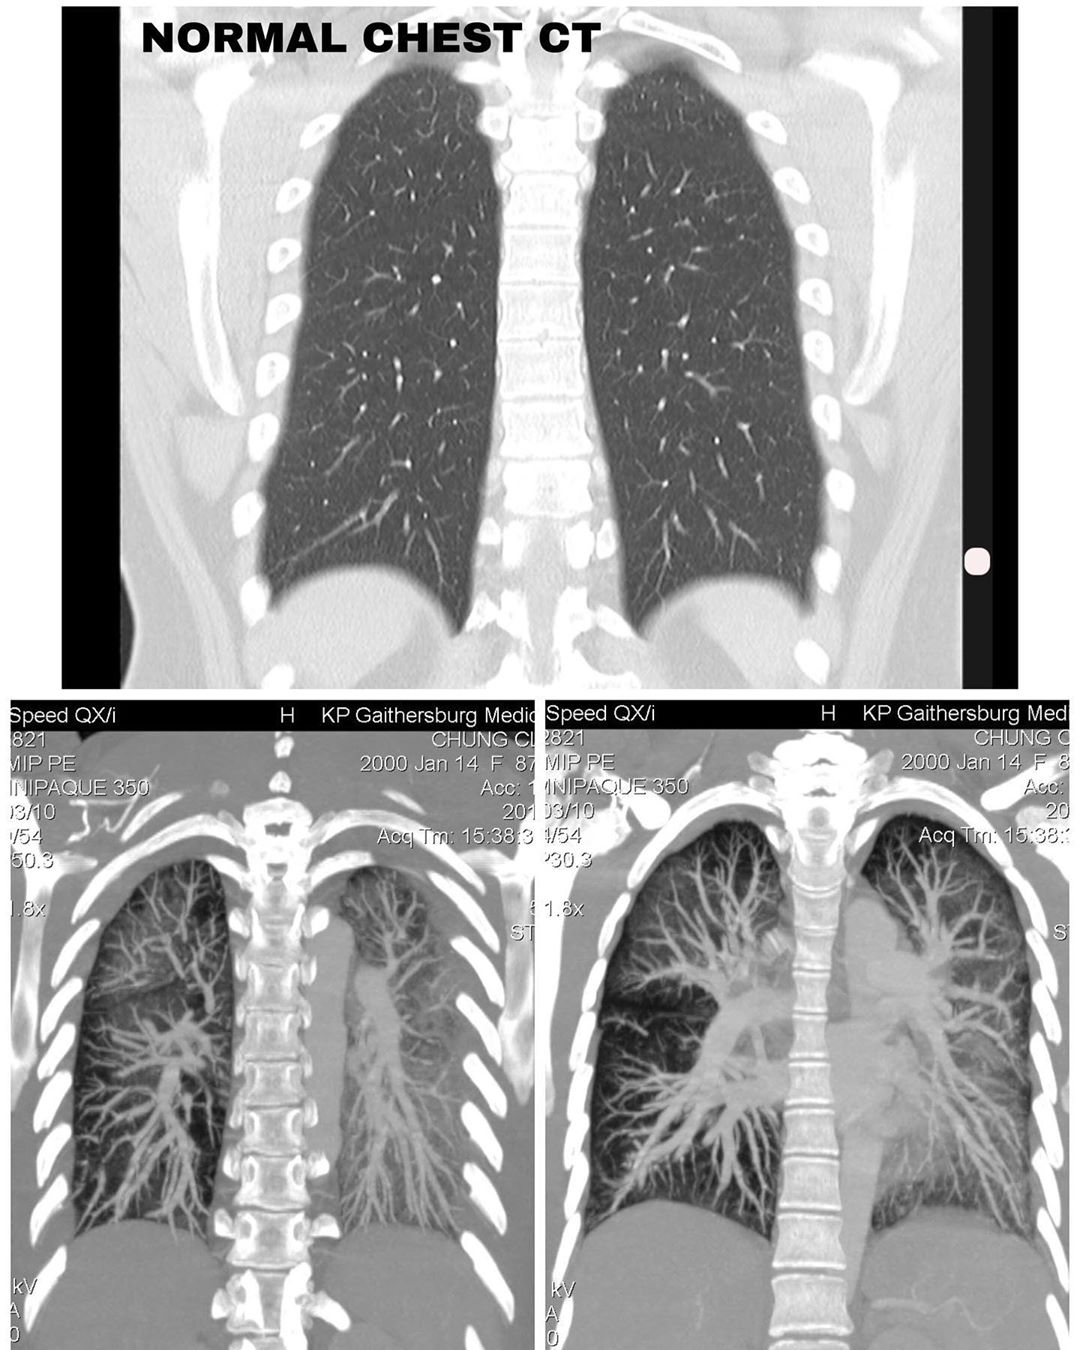

Claire 之后在 Instagram 上传她的电脑断层扫描结果,从这些X光片中可以看到,正常的肺是黑的,但她的肺已经变成是一片混浊而且发白的。

▼ 图 ①(上图为正常的肺,下图为 Claire 的检查结果。)